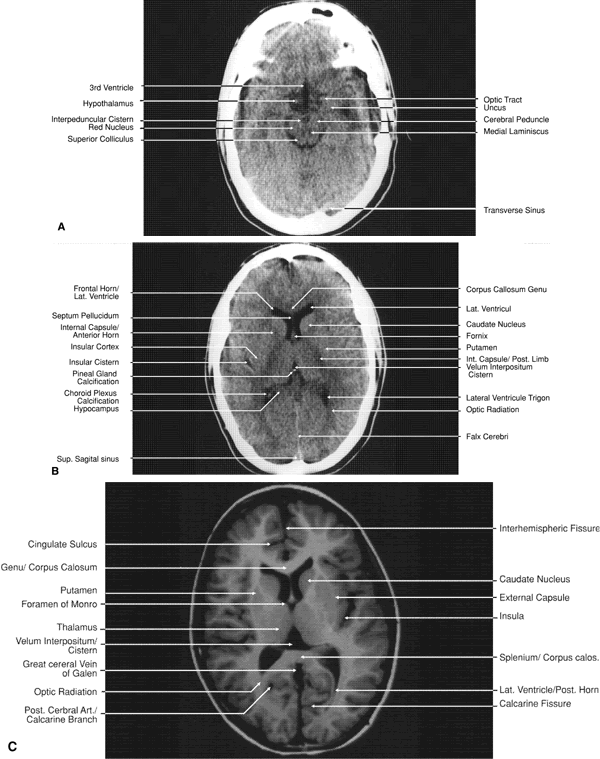

The globe is shown in Figure 12. The orbit and periorbital structures are shown in Figures 13 through 16, and the optic canal is shown in Figures 17 through 26. The cavernous sinus and optic chiasm are shown in Figures 27 and 28, and the posterior visual pathway and cranial nerves are shown in Figures 29 through 33.

Fig. 32. A. Axial computed tomography soft tissue image at the level of suprasellar cistern. B. Axial computed tomography soft tissue image at the level of thalamus. C. Axial T1-weighted image at the level of thalamus.

Fig. 33. Sagittal T1-weighted image of the brain through the interhemispheric fissure.

GLOBE

Both MRI and CT are limited in their ability to image clearly the normal intraocular structures (see Fig. 12). For the most part this is due to the small size and ultrastructural composition of these structures. The cornea and sclera cannot be differentiated from each other but are quite distinct on both MRI and CT owing to their contrast with both the vitreous and aqueous internally and the orbital fat and, if present, air trapped behind the eyelids externally. The only other readily visible intraocular structure is the lens. On CT this appears uniformly dense and similar in appearance to the sclera. However, on T1-weighted MRI, the external lens capsule can be clearly differentiated from the internal lens structure owing to the presence of a significant number of hydrogen proteins within the central portion of the lens. In addition, the normal choroid, ciliary body, and iris can occasionally be visualized on MRI but not on CT. The normal retina cannot be seen by either technique; neither can the conjunctive, Tenon's capsule, angle structures, or the vessels and nerves penetrating the globe.